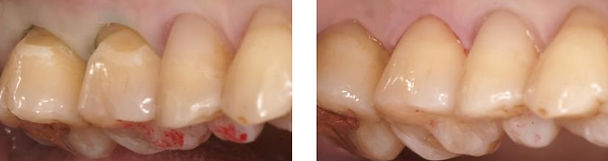

確かにこの写真のような深い楔状欠損は咬合力だけではここまで歯が削れてしまう事はあり得ず、やはり不適切なブラッシングと歯磨剤により削られたものであるのは間違いありません。

楔状欠損の修復

予後の悪いレジン修復

歯肉が極度に下がって楔状欠損が大きな範囲で生じている場合は、楔状欠損を含む露出歯根上に歯肉を移動させたり、口蓋の角化歯肉を移植して生着させる歯周外科処置を行う場合もありますが、接着性レジン修復が一般的な治療として多く施術されています。

しかし、レジン修復の予後はあまり良くありません。

修復後数年、中には数か月で、修復したレジンの輪郭から剥離やひび割れが生じているケースをよく目にします。

楔状欠損の修復例